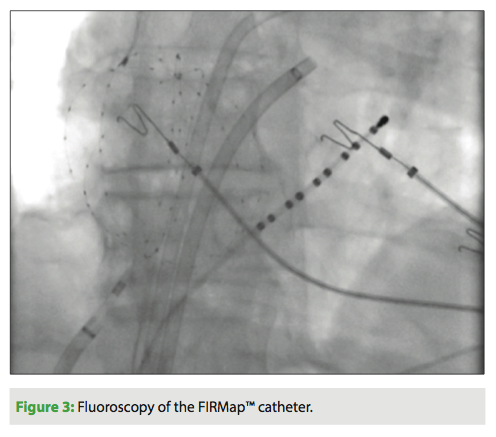

Topera’s RhythmView 3D Electrophysiological Mapping System, which received 510(k) clearance by the FDA in 2014,10 provides a dynamic representation of the electrical activity of the heart. The electrical signals of the heart are captured by placing Topera’s FIRMap™ catheter in the left and right upper chambers of the heart. The tip of the FIRMap catheter has a spherical expandable “basket” that consists of 64 evenly-spaced electrodes, which are placed over the

eight splines that form the basket and could capture the point-by-point electrical activity of the heart (Figure 3). The RhythmView Workstation analyzes the captured signals and makes a graphical display to show the specific locations in the heart which could sustain an arrhythmia.11 Early data of ablating these locations (electrical rotors) with radiofrequency has shown promising results for AF treatment.9 The CONFIRM (Conventional Ablation for Atrial Fibrillation With or Without Focal Impulse and Rotor Modulation) Trial showed higher freedom of AF after a single procedure in FIRM-guided group (82.4%) in comparison to FIRM-blinded cases (44.9%) in a median of 273 days follow-up (interquartile range: 132 to 681 days). In the CONFIRM study, 92 patients with paroxysmal or persistent AF (72%) were recruited and prospectively enrolled to FIRM-guided ablation group (n=36) or conventional ablation group (n=71; FIRM-blinded).9 Extended follow-up of the CONFIRM Trial demonstrated that freedom of AF was higher in the FIRM-guided group (77.8% [21 of 27]) versus the convectional ablation group (38.5% [25 of 65]) during a median of 890 days follow-up after 1.2 + 0.4 procedures (median 1; interquartile range: 1 to 1).12